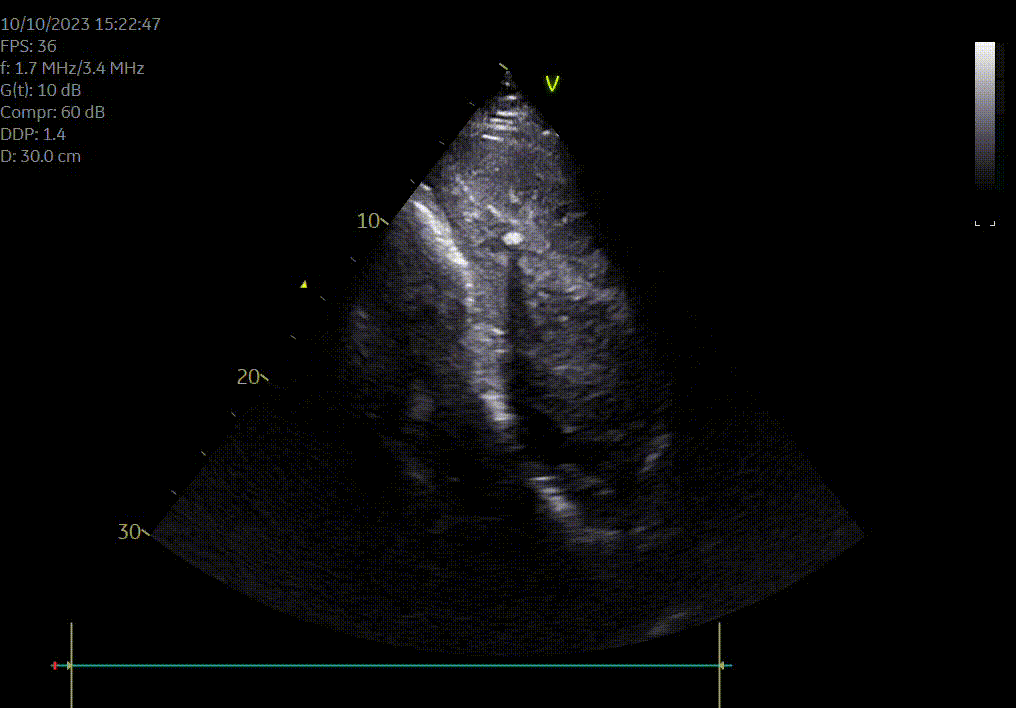

Heeft uw paard een hartruis? Dan is het aanbevolen om een echocardiografie (hartonderzoek) en een inspanningstest met elektrocardiogram (EKG) te laten uitvoeren. Zo kunnen we beoordelen of het veilig is om uw paard te berijden. Een hartruis is namelijk niet altijd een probleem. Met een echocardiografie onderzoeken we of het hart een normale structuur en werking heeft en bepalen we de ernst van eventuele klepafwijkingen.

Voor een uitgebreid hartonderzoek hoeft u niet langer naar een kliniek. Zowel de echocardiografie als de inspanningstest met elektrocardiogram kunnen eenvoudig bij u ter plaatse worden uitgevoerd.

Hartonderzoek - Echocardiografie - Electrocardiografie (EKG)